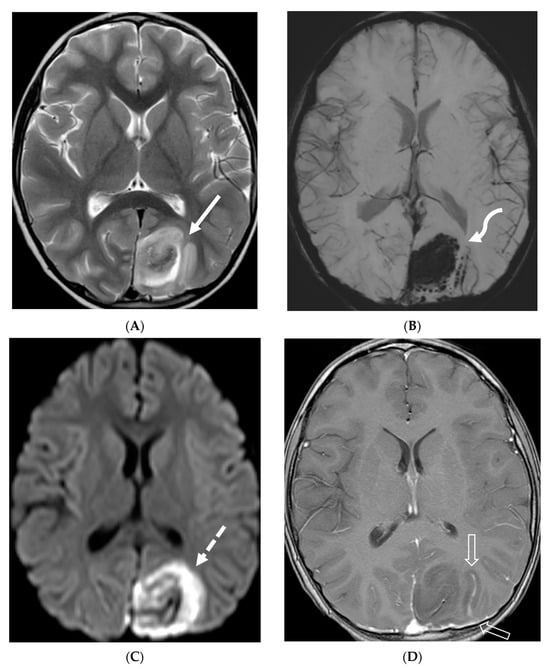

Figure 12.

Axial DWI (A), axial SWI (B), sagittal T2 (C), axial ASL (D) and coronal T1 post contrast (E): 11-day-old female presented with seizures and lethargic. Restricted diffusion is noted in the sulci along the bilateral frontal convexities, concerning for meningitis (arrows). Curvilinear susceptibility in the extra-axial spaces of bilateral frontal convexities, consistent with thrombosed cortical veins (curved arrows). Cortical T2 hyperintensity is seen in the bilateral frontal and parietal lobes with corresponding hyperperfusion in keeping with extensive cerebritis (dashed arrows). Diffuse leptomeningeal and pachymeningeal enhancement is seen (open arrows). Overall features represent meningitis and cerebritis. Cerebrospinal fluid analysis: Group B streptococcus.